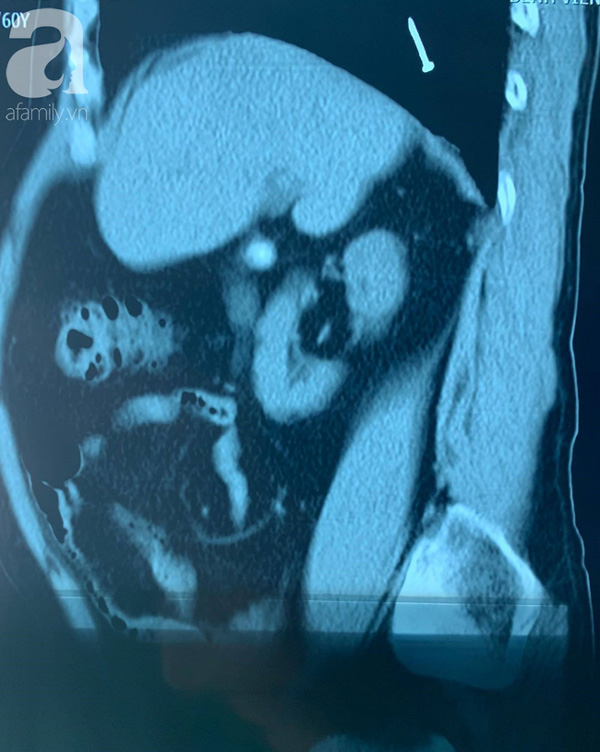

Nhưng sự thật dị vật đã rơi vào phổi.

Tại bệnh viện tuyến tỉnh, khi chụp X-quang, các bác sĩ nghi dị vật đã đi từ dạ dày xuống ruột. Tuy nhiên khi chuyển lên Bệnh viện Chợ Rẫy (TP.HCM), qua hình ảnh CT-scan kíp trực lại phát hiện chiếc đinh đã vào phổi.

Đầu chiếc đinh được ví như đầu "rắn hổ mang".

Bác sĩ Phạm Thị Vân Thanh, khoa Nội soi, Bệnh viện Chợ Rẫy cho biết qua hình ảnh nội soi, chiếc đinh lồi ra như đầu con rắn hổ mang. Ban đầu các bác sĩ sử dụng kềm để gắp dị vật ra nhưng thất bại.